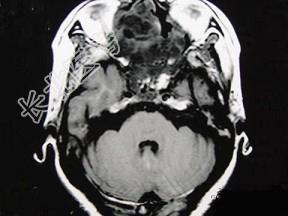

- 单项选择题女性,41岁, 鼻腔流脓涕3年,鼻部面部肿胀1年, 近来加重,MRI检查如图, 请选择最可能诊断 ( )

A、鼻腔内囊肿

B、鼻腔内出血

C、鼻腔软骨瘤

D、鼻咽癌

E、鼻腔血管瘤